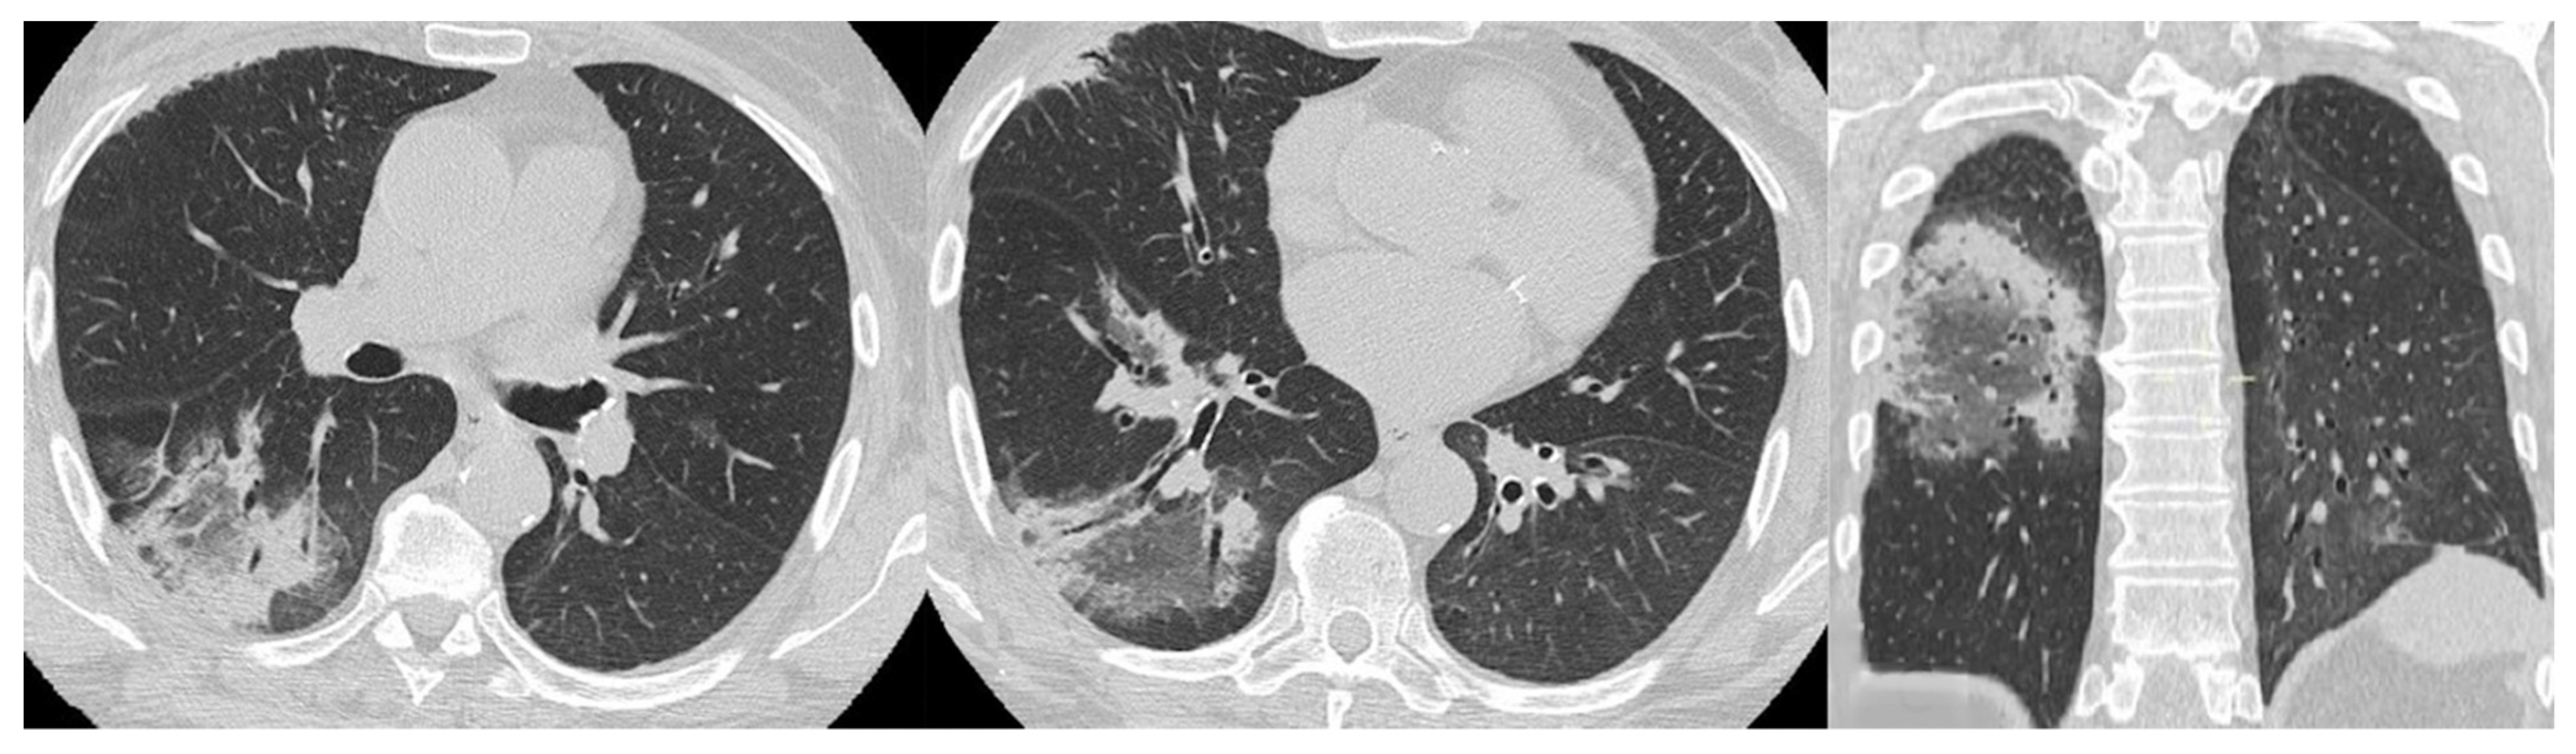

4.2.2. HRCT Findings of Patients with Anti-MDA-5 Abs

| Lesions | GGO, reticulations, consolidations | consolidations, GGOs | |

| Distribution | Homogeneous; lower lung lobes, along bronchovascular bundles and lung periphery; loss of volume of lower lobes | Patchy; peripheral lower lobes or along the bronchovascular bundles | |

| CT pattern | NSIP OP NSIP-OP UIP DAD-unclassifiable | 50% 20% 25% 10% +/− | 20% 50% 25% <5% ++ |